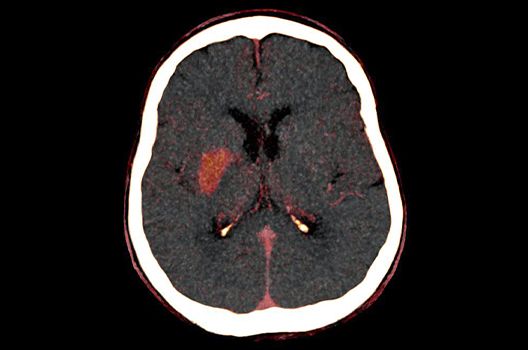

Die Hybridbildgebung mittels PET/MRT spielt insbesondere in der onkologischen Bildgebung eine wichtige Rolle. Eine mögliche Fragestellung ist die Unterscheidung zwischen einem Tumorrezidiv oder therapeutisch assoziierten Veränderungen insbesondere dann, wenn diese Frage mittels MRT alleine nicht beantwortet werden kann.

Die bildgebende Diagnostik und Verlaufsbeurteilung von Tumoren des Nervensystems ist einer der klinischen und Forschungsschwerpunkte unserer Abteilung. Eine besondere Bedeutung kommt der Hybrid-Bildgebung zu. Das Universitätsklinikum verfügt über einen integrierten Ganzkörper-PET/MRT-Scanner, der die Vorteile der MRT-Bildgebung und der Positronenemissionstherapie (PET) vereinigt. Aufgrund der langjährigen klinischen Arbeit und Forschungstätigkeit mit diesem Gerät hat die Neuroradiologie Tübingen maßgeblich zur Etablierung dieses Verfahrens beigetragen. Auch weiterhin forschen wir intensiv an neuen Methoden zur frühen Einordnung von Tumoren und insbesondere Tumorrezidiven, die mit anderen Methoden häufig nicht erfasst werden können.

- Moderne Methoden der Schlaganfalldiagnostik und -therapie

In der Neuroradiologie sind wir häufig mit Fragestellungen konfrontiert, die mehrere Fachgebiete oder auch Methoden betreffen. So arbeiten wir auch in der Forschung intensiv mit anderen Abteilungen des Universitätsklinikums zusammen, um Prozesse und Techniken bei der Diagnostik und Therapie neurovaskulärer Erkrankungen und vaskulärer Anomalien zu optimieren.